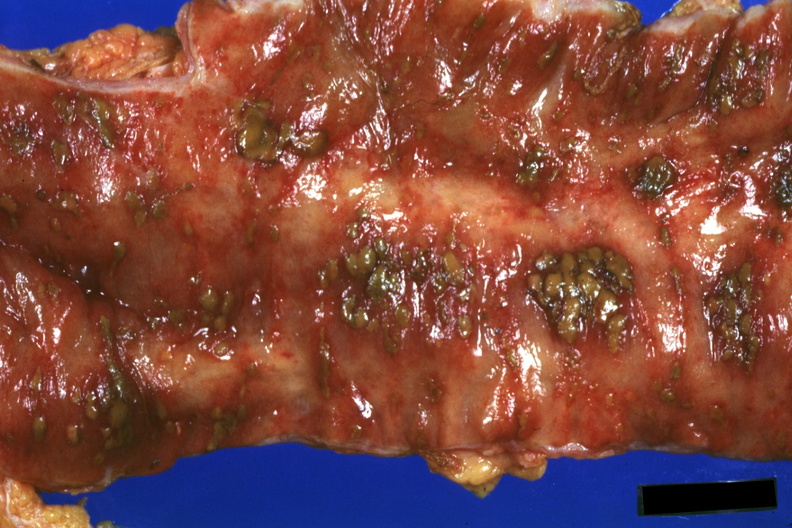

24651/33648

GROSS: GASTROINTESTINAL: Colon: Pseudomembranous Colitis: Gross natural color close-up with ulcerative lesions covered by membrane case of acute myelogenous leukemia under treatment cultures not enlightening